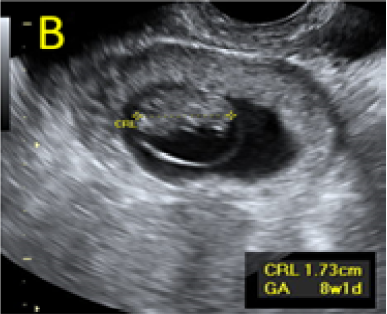

A 22-year-old secundigravida, presented to our Hospital with acute pelvic pain and vaginal bleeding. Her medical history included a 2-year prior caesarean delivery. The patient was in a stable condition and the clinical exam was unremarkable. As the urinary pregnancy test was positive, a transvaginal ultrasound scan was performed to evaluate the pregnancy location and viability. The exam revealed an empty uterine cavity but identified the gestational sac at the level of the caesarean scar with a live embryo (174 beats per minute), measuring 8 weeks and 5 days by crown-rump length. (Figures 1). Because the trophoblastic tissue was noted with an anteriorly location, urinary bladder invasion was suspected based on the ultrasonographic signs: poor identification of the bladder wall, the lack of the sonolucent space and increased vascularization with abnormal pattern (Figure 2). The patient blood tests results were normal, and beta-human chorionic gonadotropin (b-HCG) value was 145.000mUI/ml. After proper counselling and written informed consent the patient opted for a medical conservative treatment with desire to preserve her fertility.

Figure 1. A: the gestational sac is located at the level of the uterine isthmic scar, grey-scale and Power Doppler transvaginal evaluation. B: an embryo with a crown-rump length (CRL) that corresponds to 8 weeks and 1 day is found with normal fetal heart activity (C).